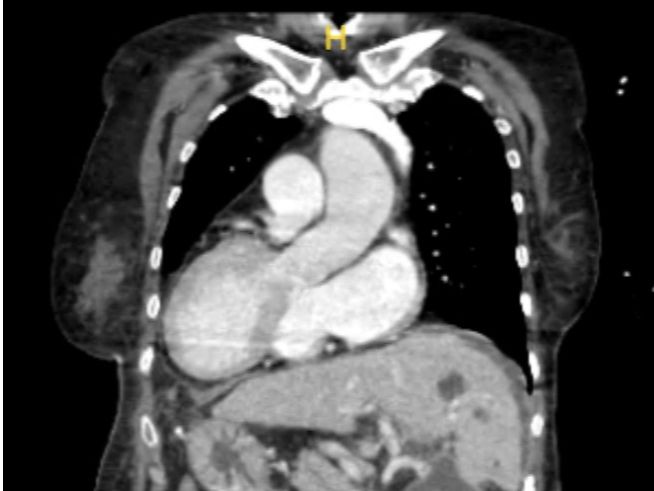

• 【人民日報】心臟在右、肝臟在左,逸仙團隊為“鏡面人”完成全內臟反位肝移植

趙女士(化名)是發生率僅為約兩萬分之一的全內臟反位人群,即俗稱的“鏡面人”。67歲的她體內的器官和常人完全相反,近日,中山大學孫逸仙紀念醫院副院長劉超教授帶領醫院肝移植團隊為身患肝功能衰竭、肝癌等疾病的趙女士成功開展了全內臟反位肝移植術。手術順利進行,團隊用精湛的技巧克服全內臟反位的困難,助“鏡面...